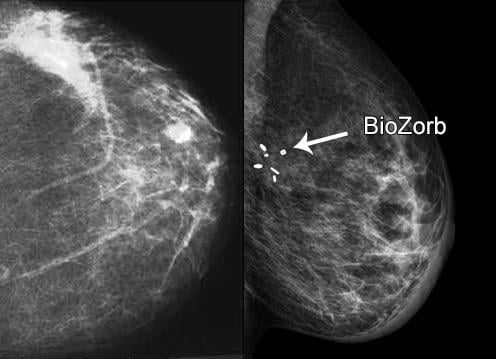

May 30, 2017 — Patients who were implanted with the BioZorb 3-D bioabsorbable marker during their lumpectomy could be treated with smaller radiation volumes than patients who did not receive the marker, according to new research. The findings were presented at the recent American Society of Breast Surgeons (ASBrS) annual meeting, April 26-30 in Las Vegas. The difference in volumes was statistically significant.

BioZorb is the first and only device, according to manufacturer Focal Therapeutics, that identifies in a reliable way the three-dimensional region where the tumor was removed. By suturing the implant to the tumor bed, the surgeon can more precisely indicate to the radiation oncologist where the cancer was located. Because of the marker's unique configuration, it allows oncoplastic surgery to be used for reconstructing the breast with the patient's own tissues, while at the same time delineating the tumor's previous location.

The marker consists of a framework made of a bioabsorbable material that holds six titanium clips. The implant serves as a guide for the radiation oncologist during planning of radiation treatments that are delivered after surgery. The device's framework slowly dissolves in the body over the course of a year or more. The marker clips remain at the surgical site and can be viewed for long-term monitoring. Studies have reported the complication rate such as infection (2-3 percent) is virtually the same as for lumpectomy surgery and follow-up radiation without the implant.